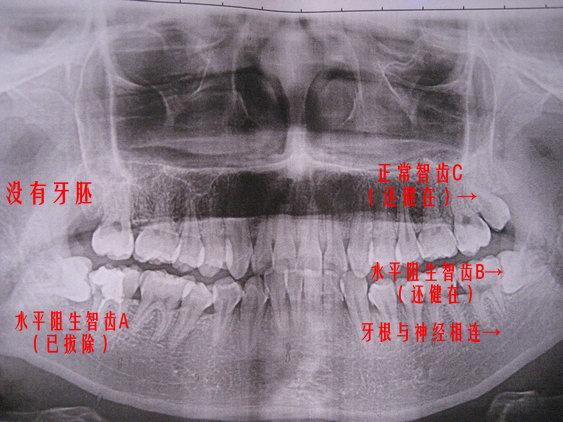

拔完智齒後能吃什麽(me)

深圳愛康健醫生表示,拔智齒後可以吃飯的,不過建議等到拔牙夠沒有明顯出血的時候,再吃飯,而且建議吃些流食、半流食,不刺激、損壞到拔牙窩的凝血塊就行,但是辛辣、刺激、堅硬的食物肯定是不能吃的,以免刺激的拔牙創口發炎,再次出現出血。